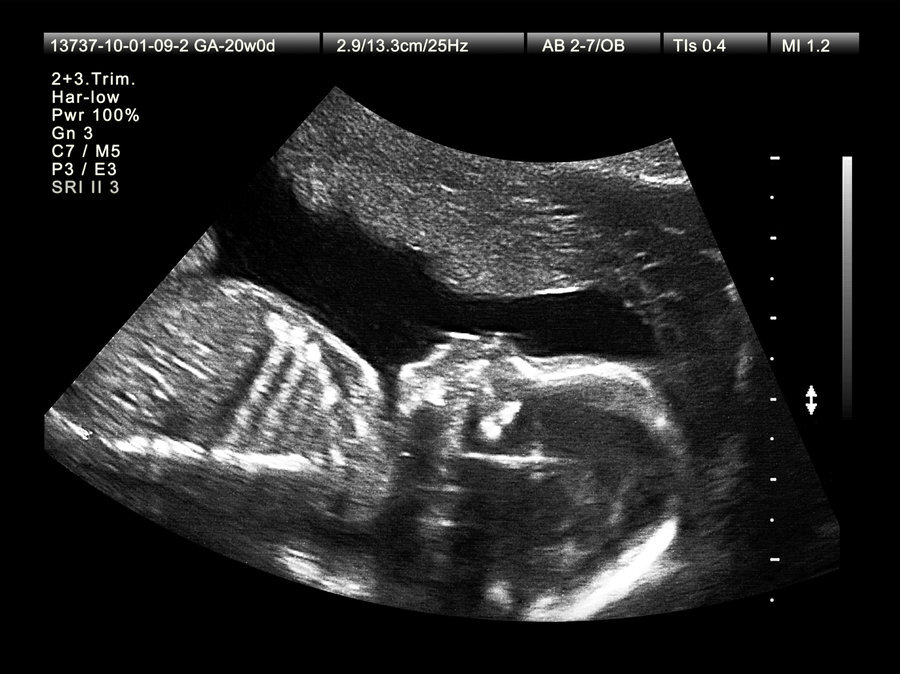

Сразу замечу, что для оценки жизнеспособности плода и выявления патологий органов важней второе УЗИ на сроке 18-22 недели. Так, что если вы противница вмешательств во время беременности, лучше все-таки сделать обязательно сделать второе УЗИ, как самое информативное.

Итак, УЗИ (ультразвуковое исследование) — исследование с помощью ультразвука, т.е. по сути механического колебания высокой частоты. Разные ткани организма человека по-разному поглощают и отражают ультразвук, и это дает аппарату возможность выдавать картинку.

В процессе исследования ткани подвергаются механическому воздействию, а также нагреваются. Значит, считать УЗИ абсолютно безопасной процедурой нельзя.

Все изыски типа допплера, 3D и дальше D требуют гораздо большего времени исследования и мощности ультразвука и категорически не рекомендованы без супер-специальных показаний.

Кроме того, черты лица еще далеки от реальных. Так что выбирайте обычное сканирование и не подвергайте ребенка дополнительным нагрузкам ради любопытства.

Результат УЗИ сильно зависит от оборудования и квалификации врача. Поэтому пусть вас не пугает любой результат УЗИ, где размеры ТВП (толщины Воротникового Пространства) больше нормативных показателей. Они измеряются в миллиметрах, и этот показатель в один и тот же день может быть разным у разных врачей из-за влияния квалификации и качества оборудования на результат измерения.

Гораздо, более важная функция у УЗИ на этом сроке - это гестационный срок. Обычно так и пишут: акушерский срок (по дате последних месячных) 12 недель, гестационный срок 12 недель и 6 дней. Именно последний реальный или истинный.